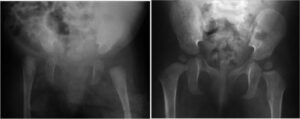

Hip surgery for arthrogryposis

Approximately 80% of children with classic arthrogryposis exhibit hip involvement, ranging from contracture of the soft tissue (tendons, capsules) to dislocation (unilateral or bilateral). Surgical interventions may include, depending on the case:

- soft tissue release, after failure of an adequate period of stretching

- Reduction of unilateral hip dislocations: This procedure is always recommended to symmetrically maintain the pelvis (for static purposes but also for sitting). It usually requires surgical reduction (open).

- Reduction of bilateral hip dislocations. There is controversy among various authors regarding the appropriateness of reduction in these cases. It is advisable to weigh the benefits (reduction can increase the patient’s ambulation potential) and risks (necrosis of the femoral heads, stiffness, recurrence, and the need for multiple interventions). In any case, it is advisable to perform the reductions at different times, given the perioperative risks associated with each individual procedure (bleeding, etc.).

- bone procedures (femoral osteotomies, pelvic osteotomies)

All interventions must be followed by adequate re-education periods and appropriate braces.